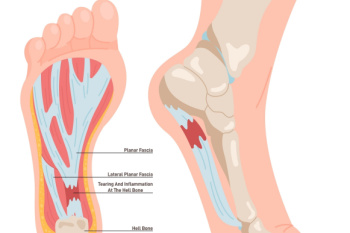

Plantar fasciitis is the inflammation of the plantar fascia, a thick band of tissue that connects the heel bone to the toes and supports the arch of the foot. This condition is a common source of heel pain, especially during the first steps in the morning or after long periods of rest. Symptoms may include sharp or aching pain in the heel or arch of the foot, often worsening with activity. Risk factors for developing plantar fasciitis include prolonged standing, high-impact activities, obesity, and wearing unsupportive footwear. Individuals with flat feet or high arches may also be more prone to this condition. If you have heel pain, it is suggested that you contact a podiatrist sooner rather than later who can accurately diagnose and treat plantar fasciitis.

Plantar fasciitis is one of the most common causes of heel pain. The plantar fascia is a ligament that connects your heel to the front of your foot. When this ligament becomes inflamed, plantar fasciitis is the result. If you have plantar fasciitis you will have a stabbing pain that usually occurs with your first steps in the morning. As the day progresses and you walk around more, this pain will start to disappear, but it will return after long periods of standing or sitting.

There are some risk factors that may make you more likely to develop plantar fasciitis compared to others. The condition most commonly affects adults between the ages of 40 and 60. It also tends to affect people who are obese because the extra pounds result in extra stress being placed on the plantar fascia.

Plantar fasciitis is one of the most common causes of heel pain. The plantar fascia is the thick band of tissue that connects the heel bone to the toes. When this band of connective tissue becomes inflamed, plantar fasciitis occurs. Fortunately, this condition is treatable.

There are several factors that may put you at a greater risk for developing plantar fasciitis. One of the biggest factors is age; plantar fasciitis is common in those between the ages of 40 to 60. People who have jobs that require them to be on their feet are also likely to develop plantar fasciitis. This includes factory workers, teachers, and others who spend a large portion of their day walking around on hard surfaces. Another risk factor is obesity because excess weight can result in extra stress being placed on the plantar fascia.

People with plantar fasciitis often experience a stabbing pain in the heel area. This pain is usually at its worst in the morning, but can also be triggered by periods of standing or sitting. Plantar fasciitis may make it hard to run and walk. It may also make the foot feel stiff and sensitive, which consequently makes walking barefoot difficult.

If you suspect that you have plantar fasciitis, meet with your podiatrist immediately. If left untreated, symptoms may lead to tearing and overstretching of the plantar fascia. The solution is early detection and treatment. Be sure to speak with your podiatrist if you are experiencing heel pain.